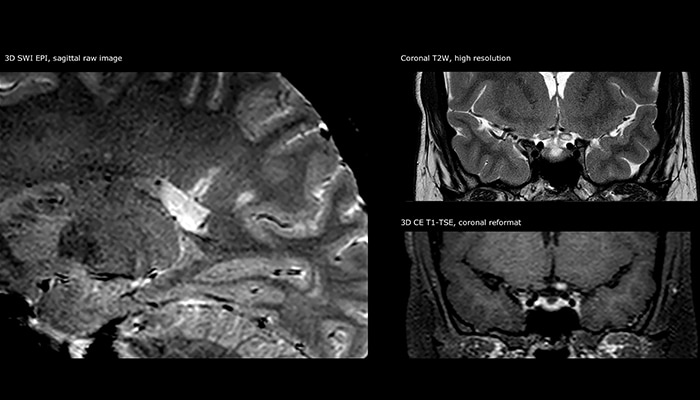

Für die MS-Bildgebung im Gehirn nutzt Dr. Savatovsky 3D-FLAIR als Basissequenz, um die Läsionen darzustellen sowie die jeweilige Situation und die Läsionsbelastung zu beurteilen. „Wir zählen die Läsionen an jeder Stelle, um zu bestimmen, ob die Kriterien der Erkrankung erfüllt sind. Dafür wird eine T2-gewichtete Sequenz verwendet, weil unsere Neurologen diese gewohnt sind. Wir vergleichen die Läsionsbelastung unter FLAIR mit einer 3D-T1-Postkontrastsequenz, damit wir feststellen können, ob die Läsionen alt oder neu sind. In der Regel verabreichen wir das Kontrastmittel vor der Aufnahme des Patienten in das System, weil sich dadurch die Untersuchungsdauer verkürzt und die Visualisierung aktiver Läsionen möglich wird, die im Allgemeinen nach mehreren Minuten deutlicher dargestellt werden. Wenn sich eine differenzielle Diagnose als schwierig herausstellt, nutzen wir weitere Sequenzen wie die Suszeptibilitätsbildgebung, da einige fokale MS-Läsionen in der Mitte eine kleine Ader aufweisen[3].“

„Die grösste Herausforderung besteht in der sachgemässen Charakterisierung der Läsion und der angemessenen Information des Chirurgen, zum Beispiel was die Position der Gefässe und der funktionellen Bereiche betrifft. Gelegentlich ist eine sehr umfassende Untersuchung notwendig, beispielsweise wenn eine Raumforderung an einem anderen Krankenhaus festgestellt wurde und der Patient anschliessend an uns überwiesen wurde. Wir führen dann eine Charakterisierung der Läsion und eine präoperative Bildgebung in einer Untersuchung durch, d.h. sowohl eine morphologische als auch eine funktionelle Beurteilung. Für die morphologische Beurteilung verwenden wir eine T1-gewichtete Prä- und Postkontrastbildgebung sowie FLAIR für die Beurteilung der Infiltration und Diffusion. Für die funktionelle Charakterisierung führen wir eine Perfusionsbildgebung, eine MR-Spektroskopie und eine suszeptibilitätsgewichtete Bildgebung durch, um Mikrogefässe oder Mikroblutungen innerhalb der Läsion aufzuspüren[4]. Für die präoperative Untersuchung führen wir eine spezifische morphologische Bildgebung durch, die mit dem Navigationssystem kompatibel ist. Je nach Position des Tumors erfolgt fMRT oder TDI.“